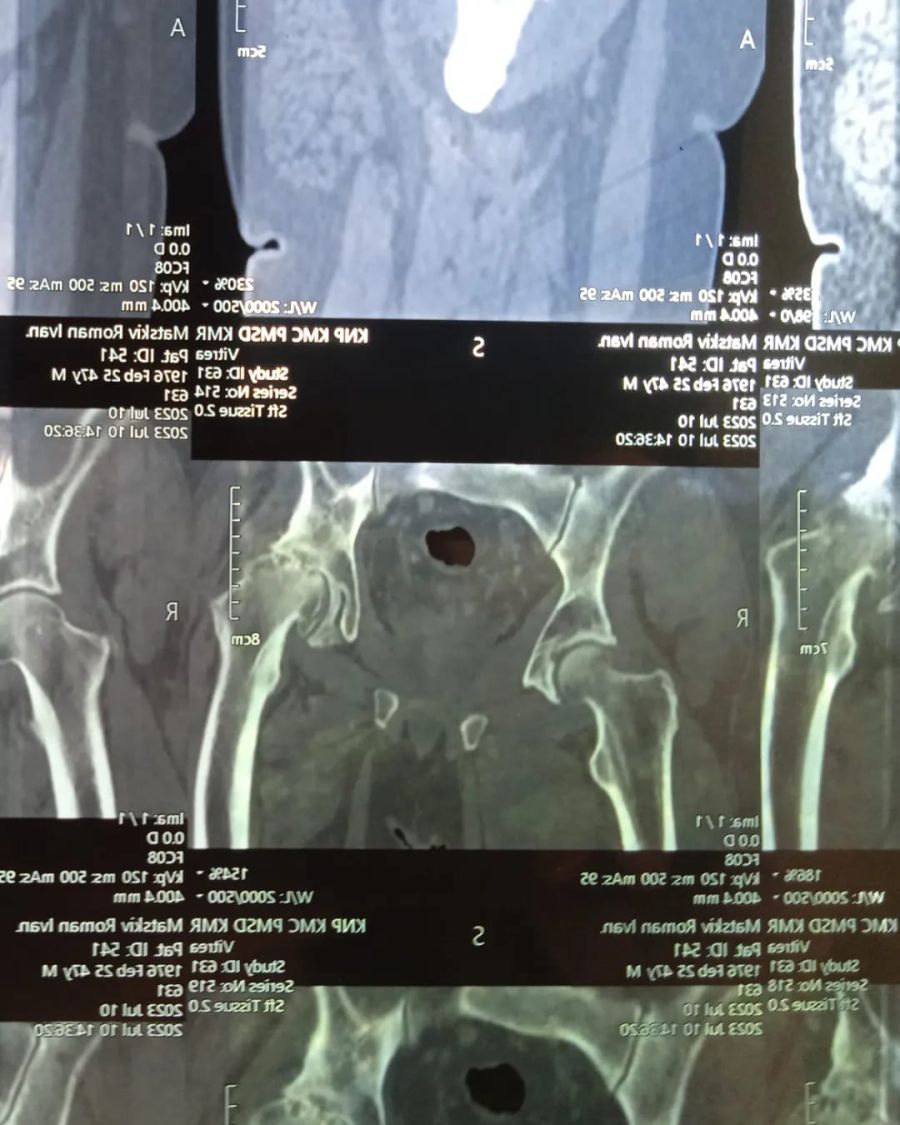

"В нашій сім'ї сталася прикра ситуація. В мого батька, Мацьків Романа, діагностувати лівобічний коксартроз IV стадії та правобічний коксартроз II стадії. Це дегенеративно-дистрофічне захворювання, при якому руйнуються хрящі, що покривають поверхню голівки стегна і вертлюжної западини. Ліва нога стала коротша на 3 сантиметра", — йдеться в повідомленні.

"Лікар сказав, що праву ногу ще можливо лікувати, і в цьому є сенс. А от ліва нога потребує ендопротезування і ,бажано, якнайшвидше, поки захворювання не почало ще більше прогресувати на правій нозі", — розповіла дочка.